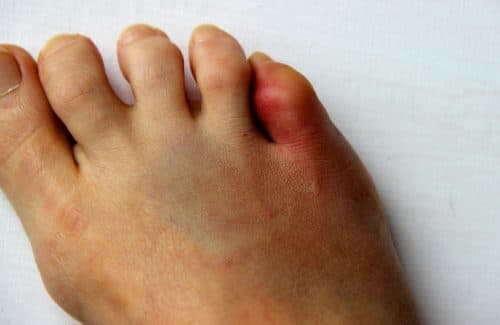

Toe Fractures

The toes play an important role in walking; due to the distal location and delicate size of the toe bones, they are vulnerable to direct injury. A toe fracture is a breakage in a bone of the toe and is a painful injury that may affect one’s ability to walk and carry out daily activities.

Toe fractures, especially those caused by traumatic injuries, are often painful and impair weight-bearing (walking and standing).  There is usually bruising, swelling and sometimes an obvious deformity of the affected toe.